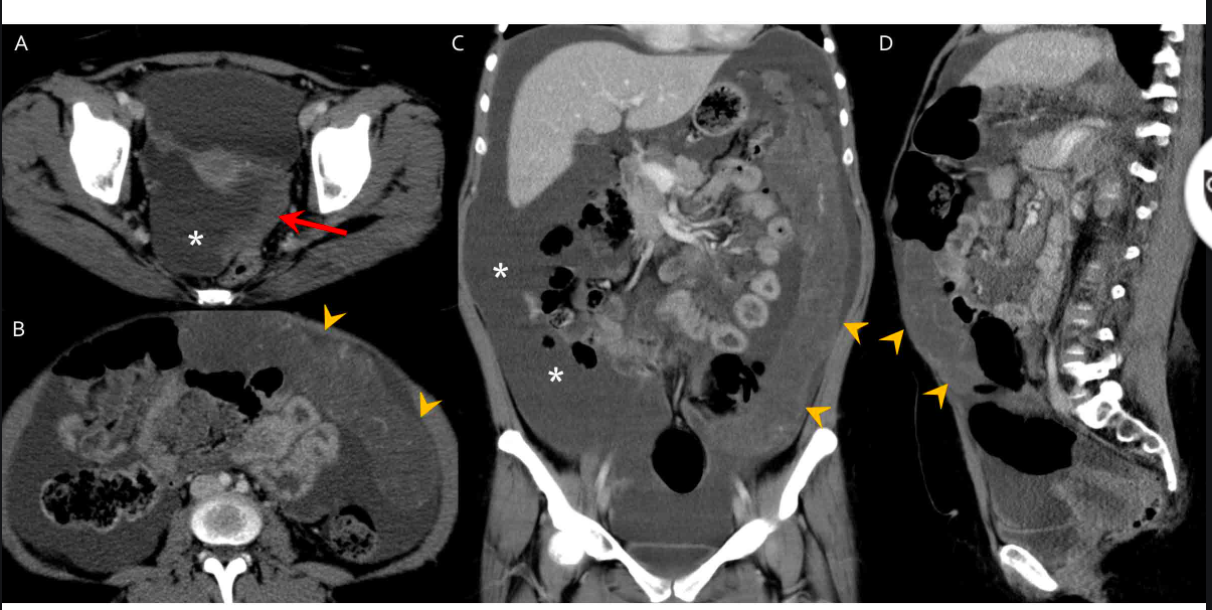

what is this?

who does it tend to occur in?

where does it tend to occur?

DDx?

Desmoplastic small round cell tumor

- aggressive malignancy usually occurring in adolescents and young adults

- CT shows multiple peritoneal-based soft tissue masses with necrosis and hemorrhage.

- Hematogenous or serosal liver mets can be present without a detectable primary tumor

- Desmoplastic small round cell tumours of the peritoneum are a rare and highly aggressive primary peritoneal malignancy.

- Epidemiology

- Desmoplastic small round cell tumour is usually seen in young adolescents and have a male predominance with a mean survival of 2-3 years.

- Clinical presentation

- A desmoplastic small round cell tumour usually presents with a palpable abdominal mass and abdominal distension with discomfort.

- It is most commonly seen to arise from the pelvic peritoneal cavity, the retrovesical or rectouterine space being the most frequent locations. The tunica vaginalis of the testis is the next most common location.

- Solitary or multiple soft tissue masses are seen with no definite organ of origin, usually in the retrovesical or rectouterine space, which enhance heterogeneously on contrast studies. Necrosis, haemorrhage and fibrous components are common.

- Peritoneal seeding, lymph nodal involvement, liver and bone metastases are common modes of spread.

Differential diagnosis

- peritoneal carcinomatosis

- non-Hodgkin lymphoma

- malignant peritoneal mesothelioma

- rhabdomyosarcoma